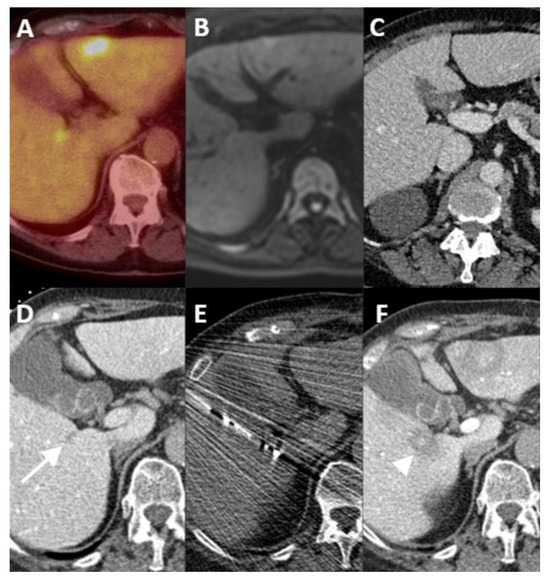

| Case No. | Tumor Size (mm) | Catheter Tip Position | Amount and Type of Contrast per Injection | Ablation Device | Institute |

|---|---|---|---|---|---|

| 1 | 20 mm | Common hepatic artery | 15–20 mL Visipaque™ | Emprint™ Microwave Ablation System, Medtronic-Covidien, Boulder, CO, USA | MD Anderson, Houston, TX, USA |

| 2 | 20 and 7 mm | Common hepatic artery | 4 mL Xenetix 300® | Cool-tip™ RFA Ablation Aystem, Medtronic-Covidien, Boulder, CO, USA | Gustave Roussy, Villejuif, France |

| 3 | 12 mm | Left-sided hepatic artery | Not specified | Cool-tip™ RFA Ablation System | Gustave Roussy |

| 4 | 9 mm | Common hepatic artery | 10 mL Xenetix 300® | Emprint™ Microwave Ablation System | Amsterdam UMC, Amsterdam, The Netherlands |

| 5 | 15 mm | Coeliac trunk | 20 mL Xenetix 300® | Emprint™ Microwave Ablation System | Amsterdam UMC |

| 6 | Not applicable | Common hepatic artery | 20 mL Xenetix 300® | Emprint™ Microwave Ablation System | Amsterdam UMC |

| 7 | Confluent | Common hepatic artery | 10 mL Xenetix 300® | NanoKnife system under ECG-gating; AccuSync model 72, AngioDynamics, Latham, NY, USA | Amsterdam UMC |

| 8 | 15 mm | Common hepatic artery | 15–20 mL Visipaque™ | Emprint™ Microwave Ablation System | MD Anderson |